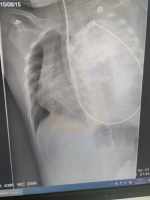

直腸腺癌誤診為高級別腺上皮內瘤變 現病史【一般資料】 女性,56,農民 【主訴】 間斷黑便10天。 【現病史】 患者及家屬訴緣于10天前無(wú)明確誘因出現黑便,大便次數增多,3-5次/日,每次量不多,數十毫升左右,無(wú)腹痛,無(wú)黏液膿性便,無(wú)鮮血便,胃部略不適,伴返酸、噯氣,無(wú)發(fā)冷、發(fā)熱,無(wú)惡心嘔吐,無(wú)咳嗽、咳痰,無(wú)頭痛頭暈,無(wú)心慌、氣短,無(wú)四肢